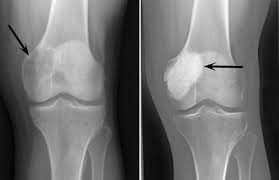

Giant cell tumor of bone is a locally aggressive tumor composed of proliferating mononuclear stromal cells and evenly distributed osteoclasts. Its severity is closely related to the pathological grade of the tumor. If pathological examination, imaging examination, etc. indicate that the tumor grade is 1, it is relatively benign. After standardized treatment, the prognosis is good and the situation is not serious at this time. However, if the tumor grade reaches Grade 2 or above, the disease is more severe and falls into the category of malignant tumors, which can easily affect the patient's quality of life and survival time.